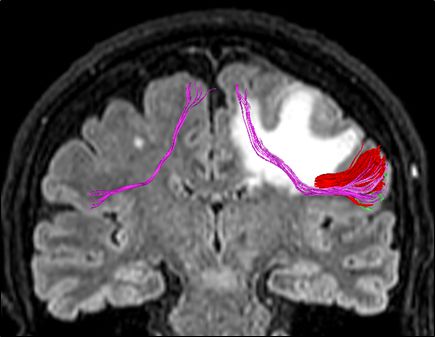

Frontal Aslant Tract. Vertical associative fiber pre-supplementary motor area to IFG. Important role in language production and motor This patient for example had a met with edema englobing the tract and had trouble initiating speech. Resolved after anti-edema drugs and resection